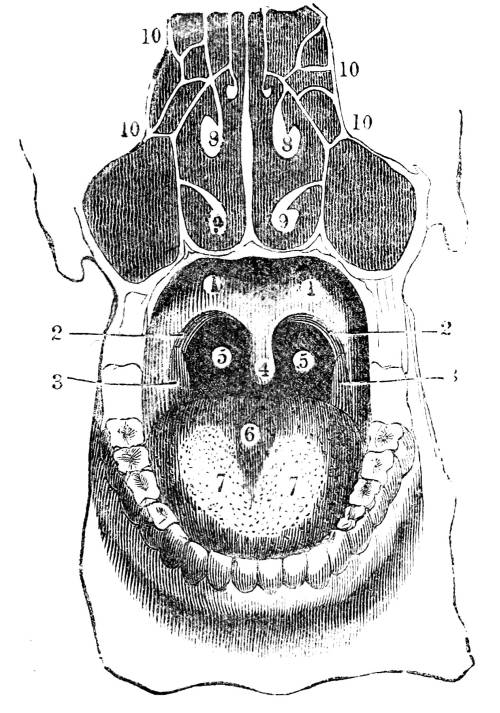

Fig. CXXXIV.—

View of the Respiratory Apparatus in

Man.

1. The Trachea. 2. The right lung. 3. The left lung.

4. Fissures, dividing each lung into, 5. Large portions

termed lobes. 6. Smaller divisions termed lobules. 7.

Pericardium. 8. Heart. 9. Aorta. 10. Diaphragm separating

the cavity of the thorax from that of the abdomen.

357. In man there are two pulmonary bags (fig.

CXXXIV. 2, 3), of nearly equal size, which, together

with the heart, completely fill the large cavity

of the thorax (fig. CXXXIV.), their external surface

being everywhere in immediate contact with

the thoracic walls. One of these bags is placed on

the right side of the body, constituting the right

lung (fig. CXXXIV. 2), and the other on the left,

constituting the left lung (fig. CXXXIV. 3). Each

lung is divided by deep fissures, into large portions

called lobes (figs. CXXXIV. 4, and CXXXV.

6), of which there are three belonging to the

right, and two to the left lung. Each lobe is

subdivided into innumerable smaller parts termed

lobules (figs. CXXXIV. 6, and CXXXV. 6), while the

lobules successively diminish in size until they

terminate in minute vesicles that constitute the

great bulk of the organ (fig. CXXXV. 8).